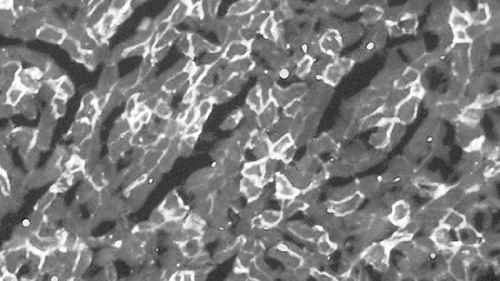

他们首先利用不致病的腺病毒做载体,将基因编辑系统输送到成年小鼠的腿部肌肉细胞内,结果显示,其腿部的抗肌萎缩蛋白水平得到一定程度的恢复,肌肉力量增加。他们又将基因编辑系统注射入小鼠的血液,这次小鼠全身肌肉得到改善,尤其是与心脏有关的肌肉,而心肌衰竭是DMD患者死亡的主要直接原因之一。

原文摘要:Duchenne muscular dystrophy (DMD) is a devastating disease affecting about 1 out of 5000 male births and caused by mutations in the dystrophin gene. Genome editing has the potential to restore expression of a modified dystrophin gene from the native locus to modulate disease progression. In this study, adeno-associated virus was used to deliver the CRISPR/Cas9 system to the mdx mouse model of DMD to remove the mutated exon 23 from the dystrophin gene. This includes local and systemic delivery to adult mice and systemic delivery to neonatal mice. Exon 23 deletion by CRISPR/Cas9 resulted in expression of the modified dystrophin gene, partial recovery of functional dystrophin protein in skeletal myofibers and cardiac muscle, improvement of muscle biochemistry, and significant enhancement of muscle force. This work establishes CRISPR/Cas9-based genome editing as a potential therapy to treat DMD.